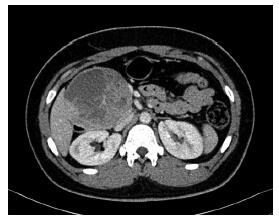

全组术前空腹血糖及血清癌胚抗原、糖类抗原199、糖类抗原125、糖类抗原242、糖类抗原724、甲胎蛋白均在正常值范围。1例神经特异性烯醇化酶水平升高(52.6 μg/L),1例组织多肽特异性抗原水平升高(148.5 U/L)。50例患者术前均行上腹部超声及CT或MR检查。超声表现为:胰腺或腹膜后类圆形低回声实性占位,肿瘤大小为10.7 cm×9.4 cm×7.8 cm,部分病变呈中央无回声的囊实性病变,有包膜;病变与周围血管界限清晰(图 1)。CT示:胰腺或腹膜后的类圆形囊实性低密度占位性病变,边界清楚,周边部分钙化;增强后肿瘤周边及实性区域呈不同程度强化,部分囊实性相间区域可见附壁结节,而囊性部分无强化(图 2,3)肿瘤大小为4.7 cm×3.0 cm;CT血管造影(CTA)示:未见周围血管受侵改变。MR示:病变内部有出血、囊性变。